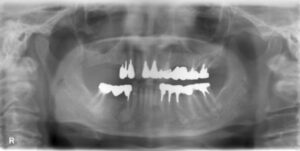

上下11本欠損症例

BEFORE AFTER 45歳男性/上下11本欠損/インプラント埋込手術 【治療内容】 10年以上放置しているむし歯の…